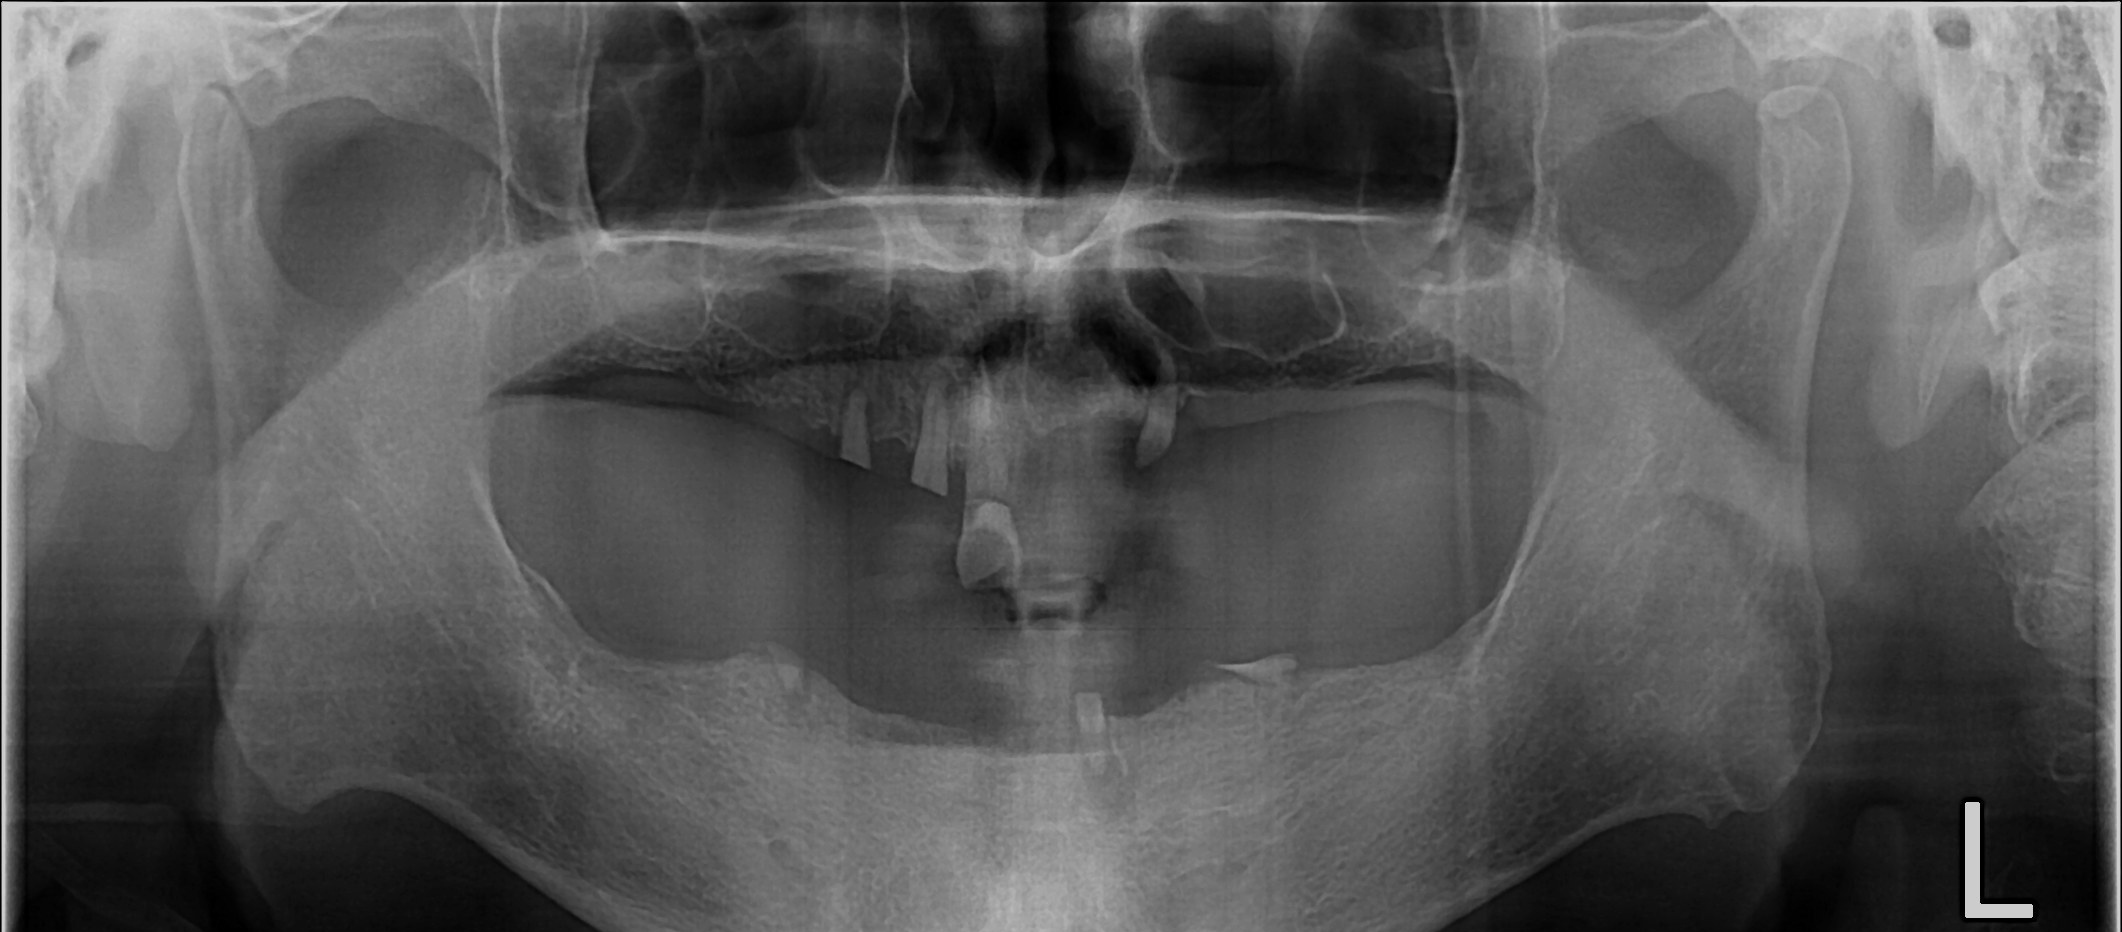

무치악 임플란트 회복

Before

무치악 임플란트 회복 Full Mouth Rehabilitation